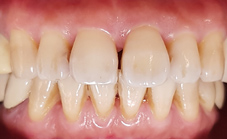

噴砂美白及居家美白前

噴砂美白及居家美白後